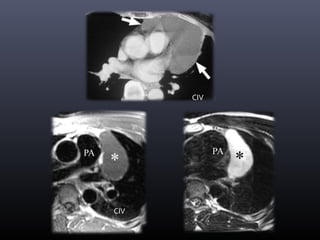

Quiste pericárdico

• Atrapamiento de parte del pericardio durante el

desarrollo

• En mediastino

• Más frecuente ángulo cardiofrénico derecho(80%)

• Apariencia TÍPICA:

 Pared fina

 No septos

 Atenuación y señal = agua (*)

 No captación de CIV

Masa pericárdica más frecuente

CIV

Divertículo pericárdico

• Muy raro

• Pericardio parietal

• Congénito o adquirido

• Comunica con la cavidad pericárdica

• Quiste pleuropericárdico migratorio (*)

• Sospecha  Variaciones de tamaño

Se desplaza con los cambios posturales

Punto de unión con pericardio (pediculado)